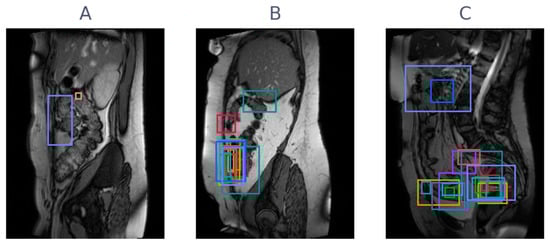

Figure 5.

Three examples of cine-MRI slice with varying levels of agreement between observers. Annotations are overlayed as boxes, with a unique color per observer. (A) A slice with high agreement for being negative (only two observers annotated), (B) a slice with high agreement for being positive in the same location, and (C) a slice with many positive annotations but in varying locations.

The analysis in this study was performed on slice-level. Clinically, this is meaningful, since it is more indicative of where adhesions are located than a patient-level analysis. If observers have high agreement on slice-level, they agree to a high degree on the location of adhesions, as well. However, Figure 5 shows (especially the right column) that even if observers agree on slice-level, there can still be disagreement about location. Figure 5 simultaneously highlights the varying annotation style, with some observers placing small boxes and others large boxes. Future studies could take this localization into account explicitly in the study design by carefully choosing the annotation type and process.